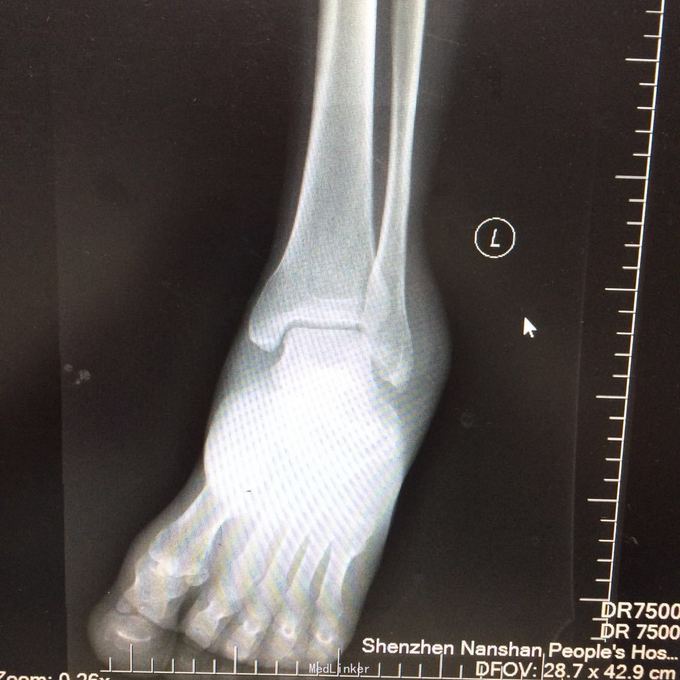

患者某某,男,49岁,因“高处坠落致全身多处疼痛、肿胀、流血2小时 1、男性壮年患者。 2、缘患者于2小时前因高处坠落致左肘、左手、右手、头面部、左胸,左足等多处受伤,即觉左肘部疼痛、活动困难、流血;左手、头面部伤口疼痛、流血;右手、左胸,左足部等处疼痛、肿胀。由家属、同事送往我院就诊,经行X线检查示:左肱骨远端粉碎性骨折,左肘关节半脱位;左手第4、5掌骨远端骨折;右手第1远节指骨基底部、第3、4远节指骨骨折,第5中节、远节指骨骨折;左跟骨粉碎性骨折。CT示:鼻中隔骨折;右侧第3--7肋骨折。急诊科予清创包扎止血,为作进一步诊治而收入院。患者受伤以来,患者精神好,无呼吸困难,无恶心、呕吐,无头晕,无面色苍白,无双下肢麻木、无力,无大小便失禁。 3、查体:T36.8 ℃ P 76次/分 R20 次/分 BP104/67mmHg。神清合作、应答切题、全身皮肤粘膜无黄染、浅表淋巴结无肿大。头颅五官无畸形,左眉弓处见一长约2cm伤口,活动性出血,巩膜无黄染,双侧瞳孔等大等圆,直径 3 mm,对光反射灵敏。鼻梁有一长约3cm纵行伤,深及皮下,伴有活动性出血;下唇部见一1*1cm组织缺损,伴活动性出血.颈软,无抵抗,气管居中,甲状腺无肿大,胸廓无畸形,右侧胸部局部压痛明显,胸廓挤压征阳性;心前区无隆起,双肺叩诊清音,呼吸音清,无干湿性罗音。心率76次/分,律齐有力,各瓣膜区无病理性杂音。腹平,腹肌软,全腹压痛、无反跳痛,肝脾肋下未及,双肾区无叩痛,无移动性浊音,肠鸣音存在,4-6次/分。脊柱、骨盆无压痛,四肢检查详见专科情况,其余肢体检查正常。双下肢生理反射存在,病理性反射未引出。

4、专科情况:左肘部中度肿胀,呈短缩、成角畸形,局部皮肤活动性出血,局部压痛明显,纵向叩击痛,左肘部可扪及骨擦感,有反常活动,左肘部活动障碍。左肩峰至肱骨外上髁上臂长度较右侧短缩1厘米,左手掌尺侧轻度肿胀,无畸形,局部皮肤正常,局部压痛明显,可扪及骨擦感,无反常活动,左手指活动正常。左侧手指肌力Ⅳ级,有牵拉痛,左上肢手指末梢血运良好,感觉略差。右手拇指、环指及尾指局部皮肤组织撕脱,渗血明显;右手中指末端损毁,局部缺失。右手手指肌力Ⅳ级末梢血运良好。左足跟部肿胀明显,局部皮肤正常,局部压痛明显,纵向叩击痛,左足跟部可扪及骨擦感,左足趾肌力Ⅳ级,无牵拉痛,左足趾末梢血运及感觉良好。 5、辅助检查:本院2015年11月14日X线检查示:左肱骨远端粉碎性骨折,左肘关节半脱位;左手第4、5掌骨远端骨折;右手第1远节指骨基底部、第3、4远节指骨骨折,第5中节、远节指骨骨折;左跟骨粉碎性骨折。CT示:鼻中隔骨折;右侧第3--7肋骨折;左下肺挫伤。

1、左肱骨远端粉碎性开放性骨折;2、左肘关节半脱位;3、左手第4、5掌骨远端骨折;4、右手第1、3、4远节指骨骨折;5、右手第5中节、远节指骨骨折;6、鼻部软组织挫裂伤;鼻中隔骨折;7、右侧第3--7肋骨折;8、左跟骨粉碎性骨折;9、左眉弓软质挫裂伤;10、左肺挫伤;11、脑震荡。 1.完善三大常规、PT四项、生化等各项常规检查; 2.完善CT检查,予抗破伤风、抗感染、镇痛、止血等对症支持治疗; 3.请口腔、耳鼻喉、眼科等相关科室会诊; 4.请示上级医师,指导下步治疗。 手术时间:2015年11月15日 术后诊断:左肱骨远端开放性粉碎性骨折 麻醉方式:全身麻醉 手术名称:左肱骨远端开放性粉碎性骨折清创缝合外固定架固定术 手术时间:2015年12月25日 术后诊断:左肱骨远端粉碎性骨折 麻醉方式:臂丛麻醉 手术名称:左肱骨远端粉碎性骨折切开复位内固定术 。 手术时间:2015-12-3 术后诊断:左跟骨粉碎性骨折;左肱骨远端粉碎性开放性骨折;左肘关节半脱位;左手第4、5掌骨远端骨折;右手第1、3、4远节指骨骨折;右手第5中节、远节指骨骨折;右足拇趾撕脱骨折并趾间关节脱位;鼻部软组织挫裂伤;鼻中隔骨折;右侧第3--7肋骨折;左眉弓挫裂伤;左肺挫伤;脑震荡。 麻醉方式:腰硬联合 手术名称:左跟骨粉碎性骨折切开复位钛板内固定术